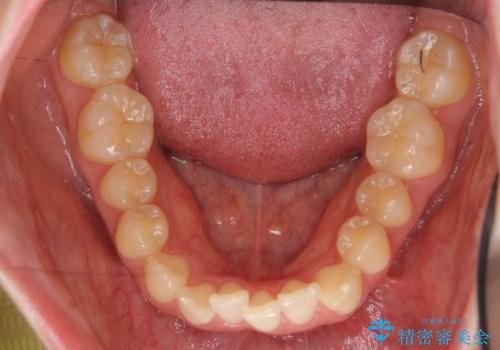

- 前歯のねじれを主訴に来院。

前から2番目の歯がねじれて下の歯の内側に入っていました。

また、奥歯のかみ合わせが上の奥歯が若干前に並んでおり、それで前歯が入りきらずにねじれていました。

歯を抜かずに奥歯を後ろに下げてマウスピースで矯正しています。